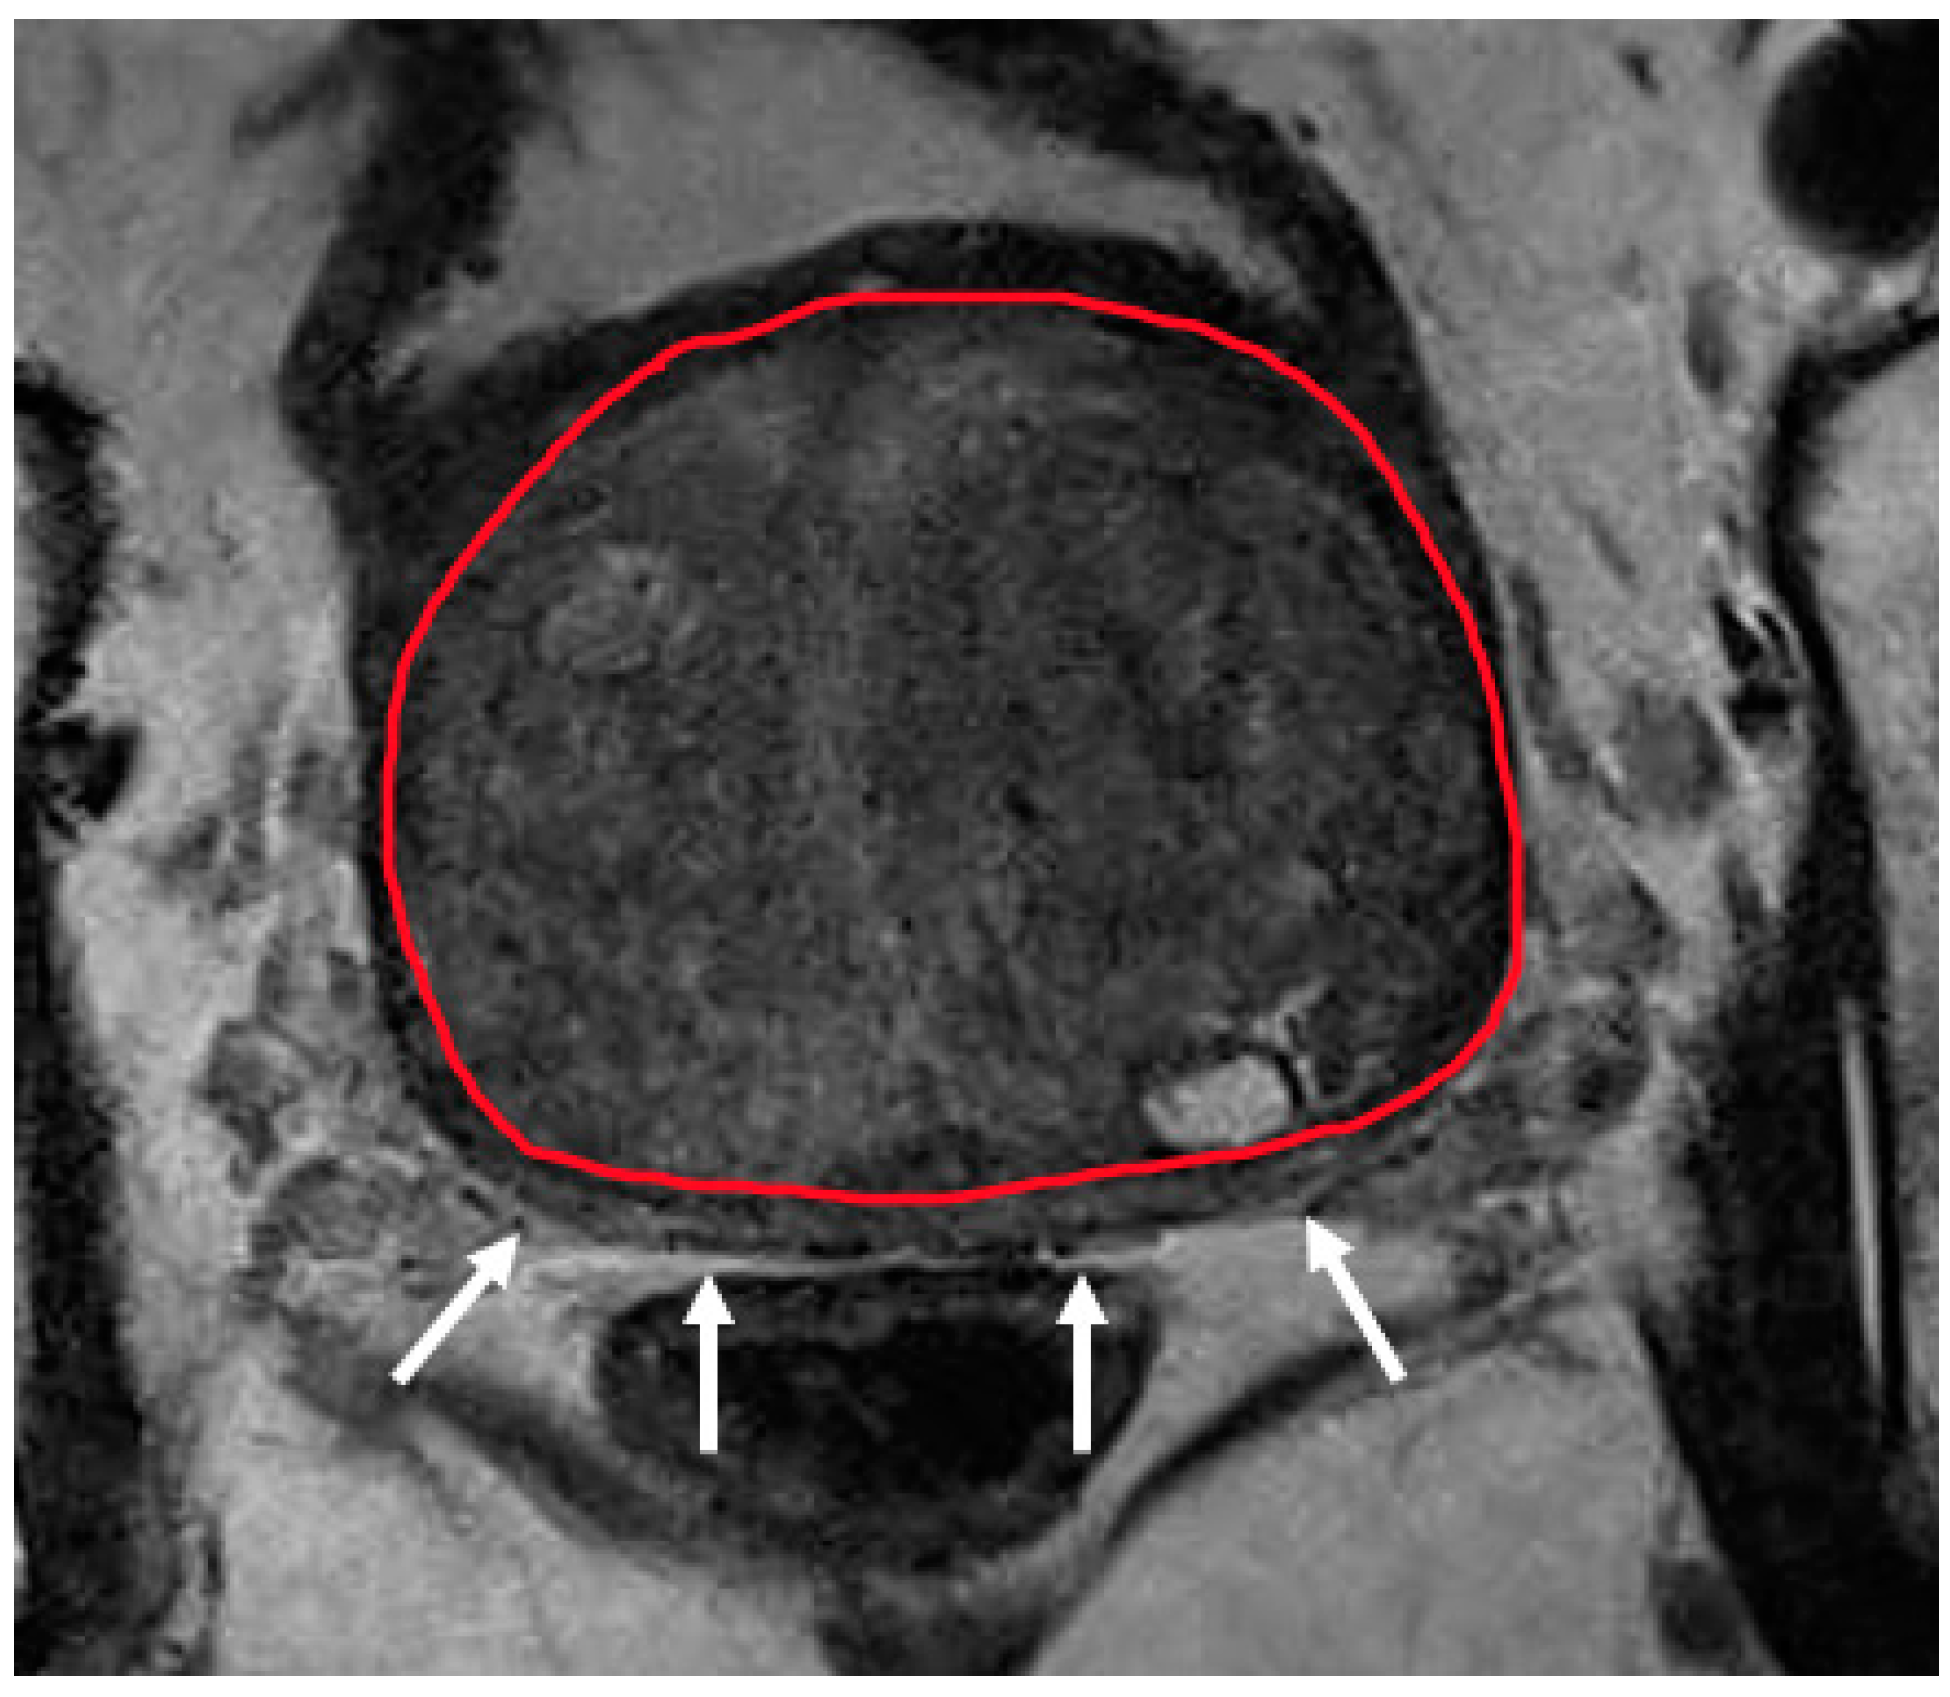

Recently, several studies have compared different deep CNN models on zonal segmentation. Cuocolo et al. [48] compared three deep learning methods, UNet, an efficient neural network (ENet) [60], and efficiently residually factorize ConvNet (ERFNet) [61] in the PROSTATEx public dataset. ENet (0.91, 0.87, 0.71) and UNet (0.88, 0.86, 0.70) were more accurate than ERFNet (0.87, 0.84, 0.65) in terms of DSC (for WG, TZ and PZ, respectively), while ENet outstood the other two methods, with faster convergence speed and fewer parameters. Saunders et al. [49] compared the performance of independent training, transfer learning, and aggregated learning based on 3D and 2D U-Net models, on the premise of limited training data. In addition, 3D U-Net was found to be more robust to a small sample size (five training cases) than 2D U-Net by an average DSC of 0.18, while transfer learning and aggregated learning (similar DSC: 0.73, 0.83, 0.88 for PZ, CG, WG, respectively) both outperformed independent training (DSC 0.65, 0.77, 0.83) when using five internal training cases. Predictably, automated segmentation between PZ and TZ can become challenging in cases where tumours span across both zones, since false positives like prostatitis in the PZ reduce its normal high T2 signal to become isointense to the TZ, whereas severe benign prostatic hypertrophy in the TZ compresses the PZ, reducing the ability to discriminate between the two zones (Figure 2, Figure 3 and Figure 4).

Figure 4.

Severe hypertrophy of the transition zone (segmented in red) compressing on the peripheral zone which appears as a thin sliver (white arrows). Reduced visualisation of the peripheral zone in this case can make zonal segmentation challenging.